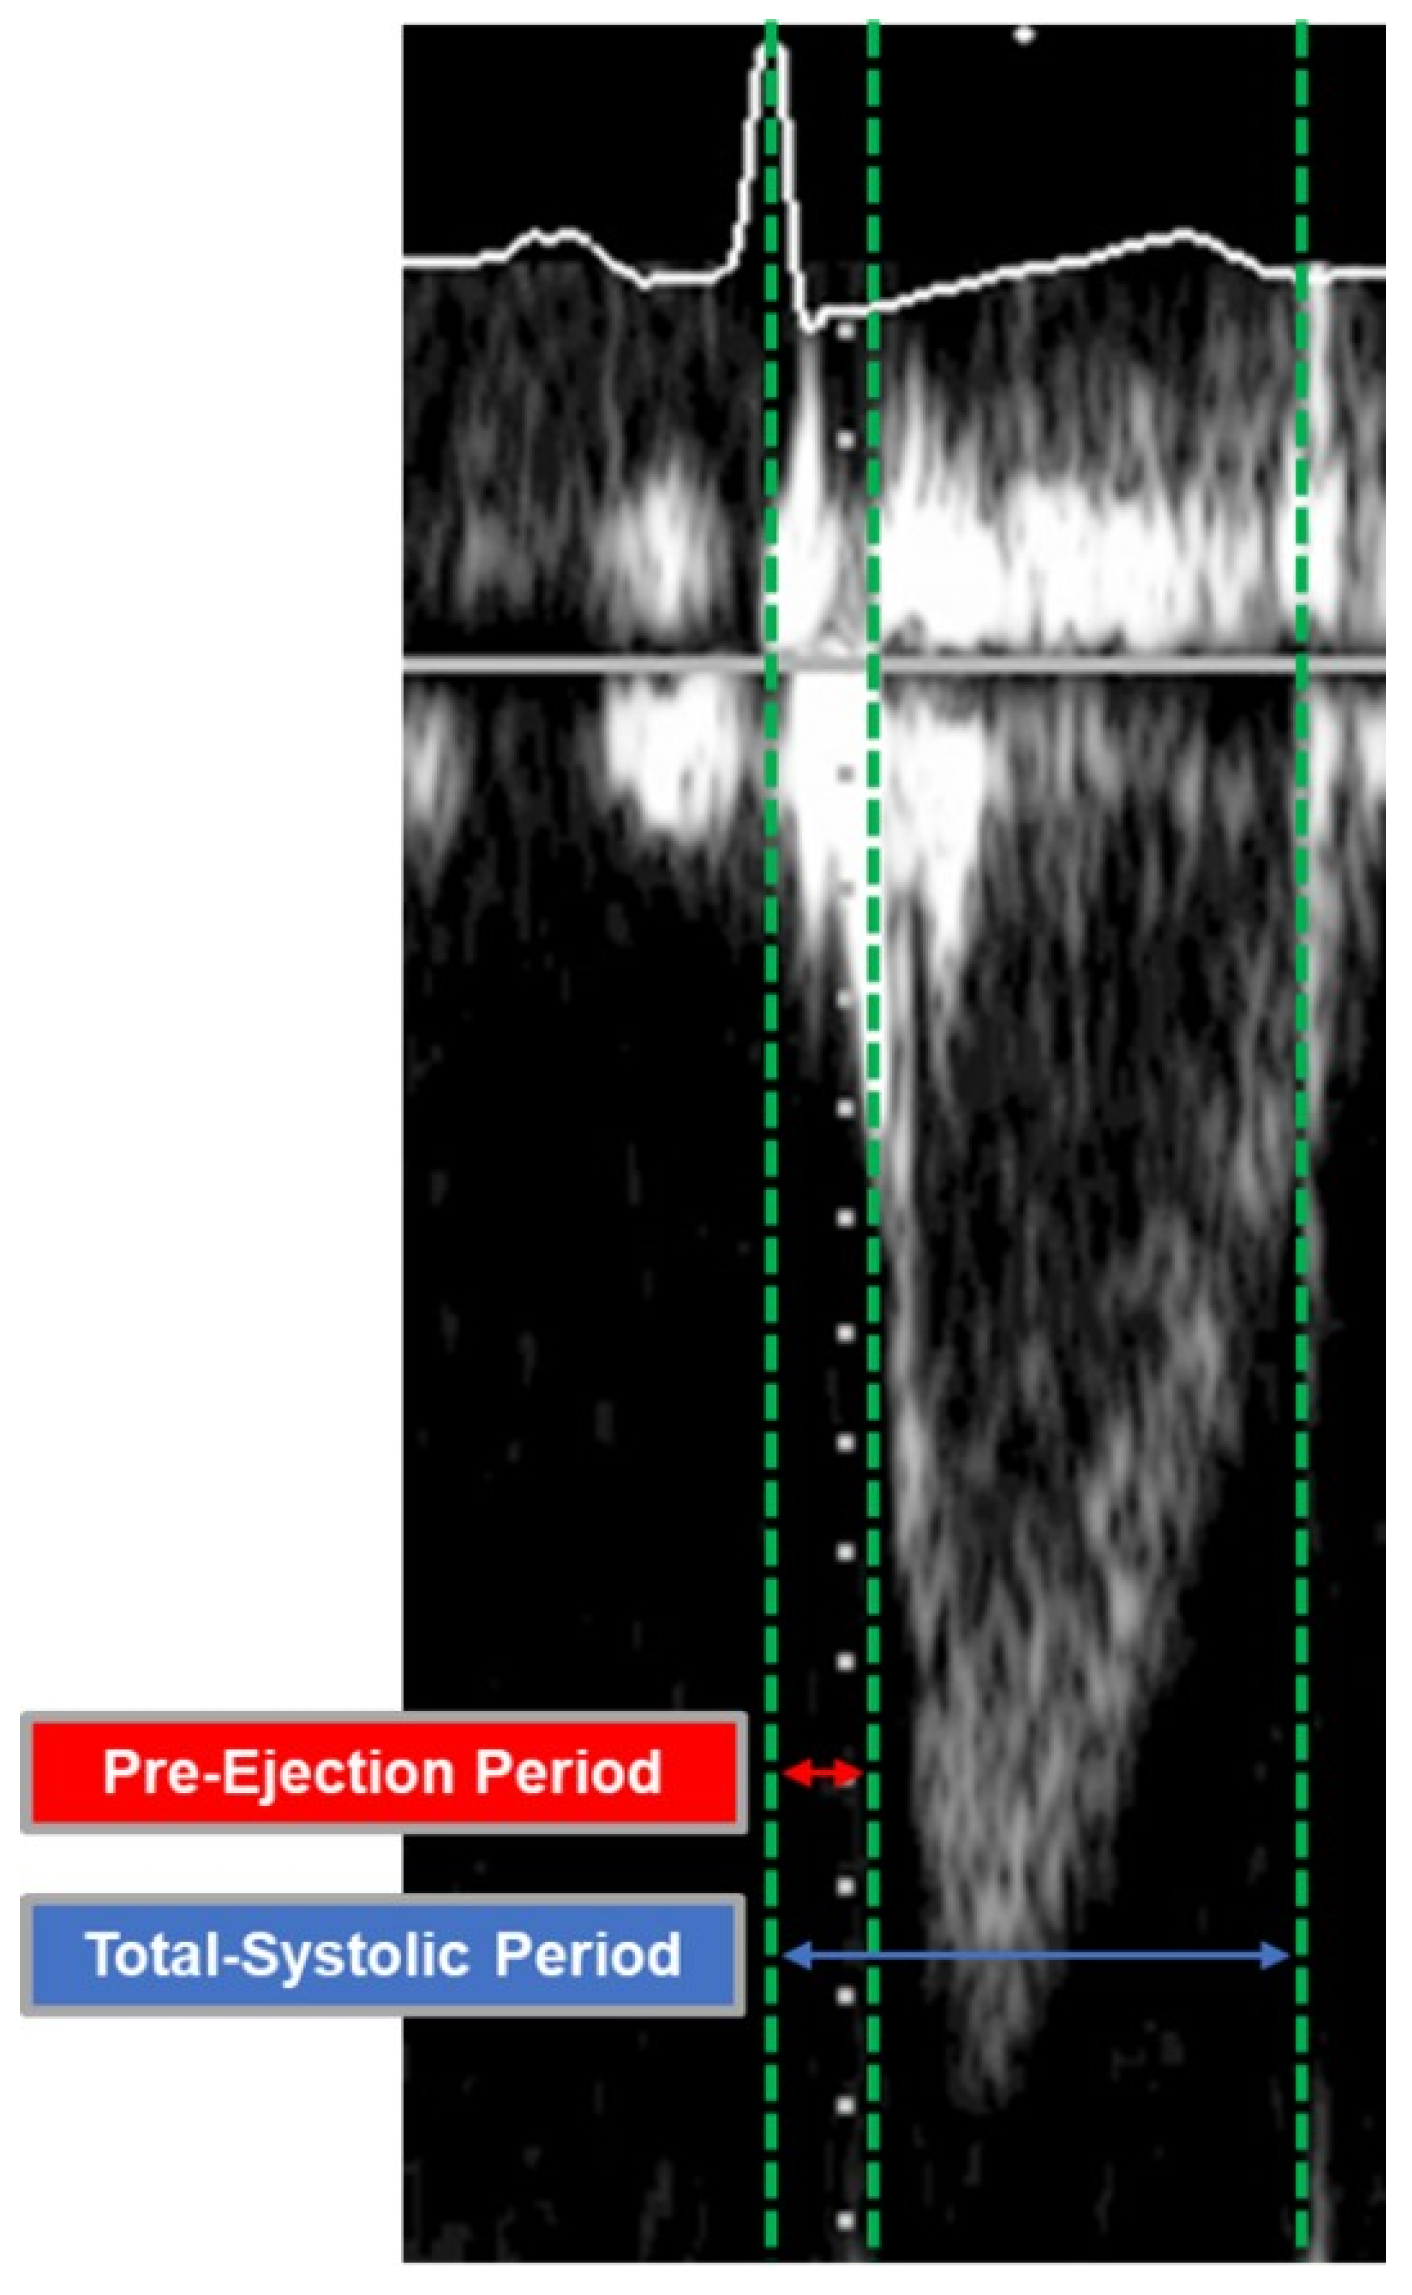

A pulsed wave Doppler was positioned over the aortic valve in apical five-chamber view and under constant three-lead ECG tracking. Recorded clips were then transferred to a separate workstation (IntelliSpace Cardiovascular Ultrasound Viewer, Philips Healthcare, Amsterdam, The Netherlands) to measure the pre-ejection period (R wave in ECG to flow onset, ms) and the total-systolic period (R wave in ECG to end of flow, ms) of the left ventricular outflow tract (Figure 2) []. Heart rate (HR, bpm) was calculated automatically by the software.

Figure 2.

Assessment of the Pre-Ejection and the Total-Systolic Period of the Left Ventricular Outflow Tract. A pulsed wave Doppler was positioned over the aortic valve in apical five-chamber view.